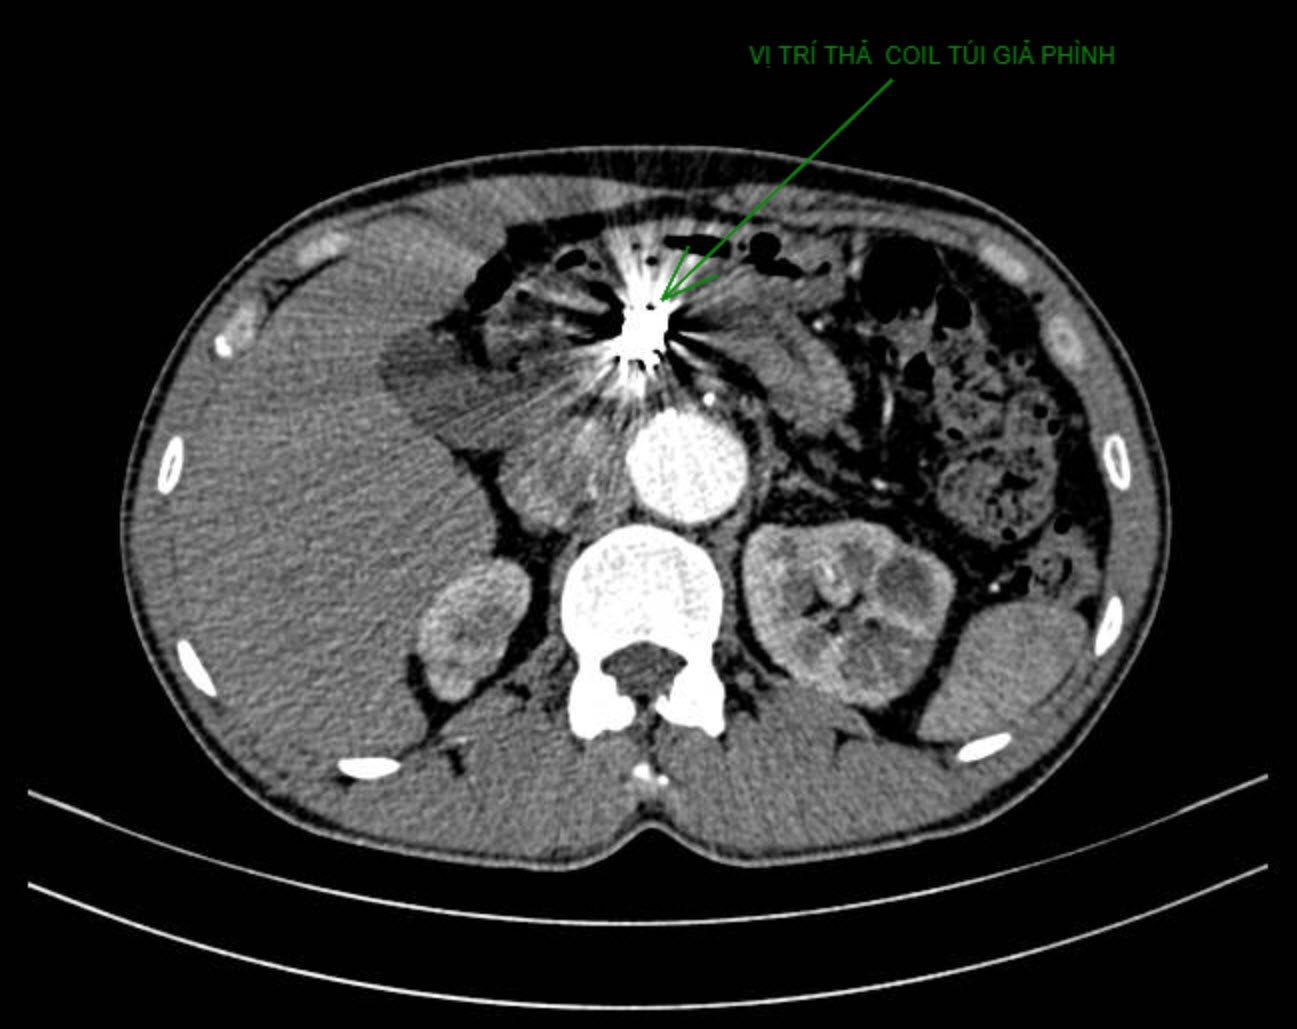

Ở lần can thiệp thứ 2, các bác sĩ đã đặt 6 coil với chiều dài hơn 3,6 mét (mỗi coil dài 60 cm, đường kính 1mm) để lấp đầy khối giả phình. Kỹ thuật đặt coil thuận lợi do đã có khung hợp kim đặt lần 1 làm khung chậu. Sau can thiệp, khối giả phình được lấp đầy, không còn hoạt động. Động mạch lách được bảo tồn; động mạch gan chung bị tắc hoàn toàn (nằm trong dự đoán) nhưng gan không bị ảnh hưởng do vẫn còn tĩnh mạch cửa nuôi dưỡng. Một ngày sau, người bệnh được xuất viện trong tình trạng sức khỏe ổn định, không còn nguy cơ biến cố do túi giả phình đã được giải quyết triệt để.

Hình CT sau thủ thuật đặt coil lấp đầy khối giả phình